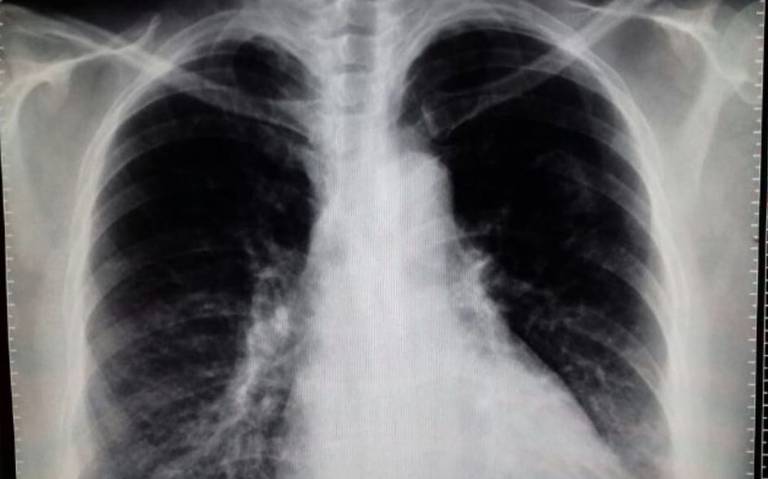

Ecografía pulmonar como predictor de terapia intensiva en neumonía por COVID-19

28 diciembre 2021

En el análisis univariado se observó una asociación entre la puntuación de la ecografía pulmonar (EP), los niveles elevados de procalcitonina y péptido natriurético cerebral y el ingreso a terapia intensiva. En el análisis multivariado solo la puntuación de EP fue un predictor independiente de requerimiento de terapia intensiva. MEDICINA (Buenos Aires), diciembre de 2021